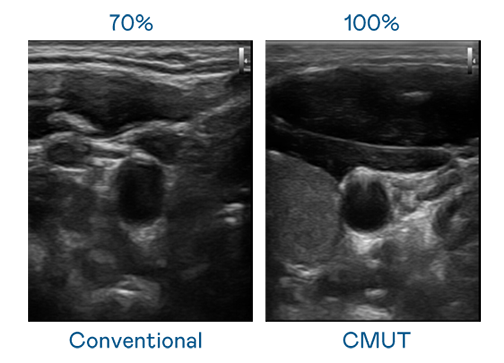

CMUT 技术是一种用电容式微机电元件来产生超音波讯号的技术。与传统 PZT 压电式技术相比,CMUT 频宽增加 30%,更宽频的超音波讯号让影像解析度大幅提升,是实现高影像品质医疗超音波扫描、促进精准医疗发展的关键技术。

大频宽带来超清晰影像

超音波影像的解析度高低,首先取决于探头能发出的讯号频宽。极速3D CMUT 可提供高清晰的超音波讯号,提供高频宽、高灵敏度、影像纹理细节更高的超音波影像,协助医护人员缩短影像判读时间及利用精准的医疗影像进行诊断。